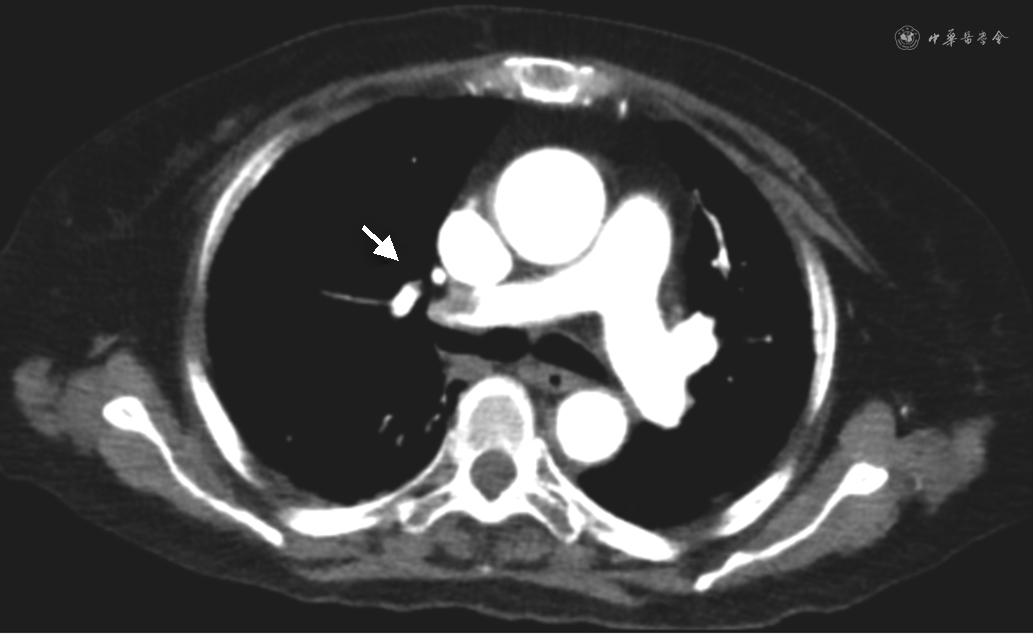

入院次日患者诉头晕、呼吸困难,测 SpO2 92%(未吸氧),血气示pH 7.45,氧分压 67 mmHg,二氧化碳分压32 mmHg,乳酸 4.4 mmol/L,心肌肌钙蛋白(cTnI)正常范围,N末端B型钠尿肽原(NT-proBNP)281 pg/ml,超声示双侧股浅静脉至胫后静脉起始段血栓形成。CT肺动脉造影(CTPA)示右肺动脉主干及双肺多发分支栓塞(图2),左肺下叶团片影伴小空泡(图3);胆囊底壁局限性缩窄(图4A)。监测患者血压显著降至85/63 mmHg,持续时间>15 min,心率90 次/min,呼吸25 次/min,意识清晰,考虑为急性肺栓塞,肺栓塞严重程度指数(PESI)评分至少为100分,简化的肺栓塞严重程度指数(sPESI)评分至少1分,血流动力学不稳定,危险分层为高危。转入监护病房后血压逐渐回升至125/66 mmHg,予普通肝素持续静脉泵入,维持APTT 50 s左右,呼吸困难缓解,3日后改为依诺肝素钠4 000 U每12小时皮下注射。